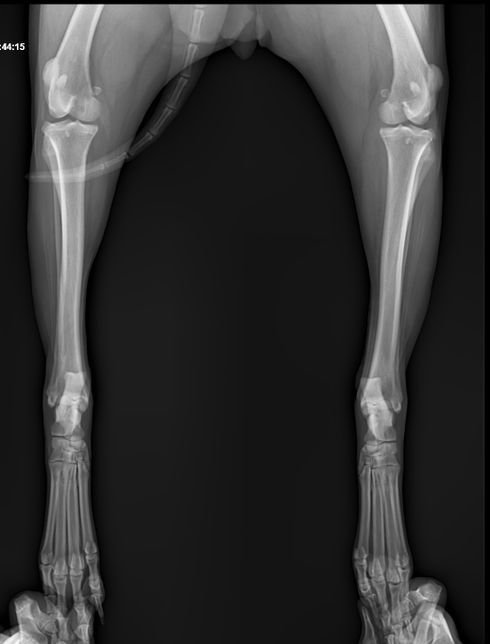

Q. 강아지 엑스레이상 문제 없는데 발이 왜 이상할까요?계단 오르다 발을 헛딛고 못 딛어서 엑스레이찍어 봤는데 엑스레이상 문제는 없다고 하셨어요 하지만 현재 발 모양이 이상해서요 인대 문제라고 하셨는데 인대로 인한 발 모양이 변했다면 언제쯤 다시 돌아 올까요? 삼일째 되는 날 발을 중간중간 딛기는 하는데..너무 걱정되네요 다른 의견도 듣고 싶어 질문 합니다.다친발 사진정상 발 사진

• 강아지 엑스레이상 문제 없는데 발이 왜 이상할까요?의 0번 째 이미지

• 강아지 엑스레이상 문제 없는데 발이 왜 이상할까요?의 1번 째 이미지

• 강아지 엑스레이상 문제 없는데 발이 왜 이상할까요?의 2번 째 이미지

• 강아지 엑스레이상 문제 없는데 발이 왜 이상할까요?의 3번 째 이미지